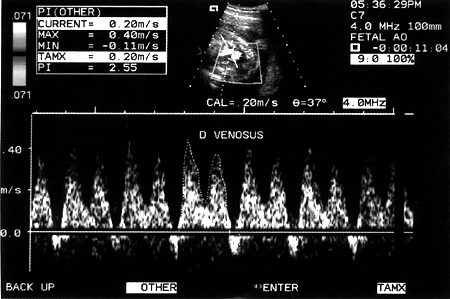

Εικόνα 1. Φυσιολογική Doppler κυματομορφή του φλεβώδη πόρου με τα κύματα "s", "d" & "a".

Στα προχωρημένα στάδια της παθοφυσιολογίας της εμβρυικής υπολειπόμενης ανάπτυξης, οι αντιρροπιστικοί μηχανισμοί του εμβρύου ανεπαρκούν, με σοβαρές επιπτώσεις για το έμβρυο, αν αυτό δεν γεννηθεί αμέσως. Η μελέτη των εμβρυικών φλεβών και συγκεκριμένα της ομφαλικής, της κάτω κοίλης και του φλεβώδους πόρου, ουσιαστικά αντικατοπτρίζουν τη λειτουργικότητα της δεξιάς κοιλίας.(21) Ωστόσο, ο φλεβώδης πόρος, σύμφωνα με τους περισσότερους μελετητές, αποτελεί το αγγείο εκλογής του φλεβικού συστήματος που αντανακλά καλύτερα τη μεταφορά οξυγονωμένου αίματος από την ομφαλική φλέβα στο δεξιό κόλπο.(22) Συγκεκριμένα, η φυσιολογική Doppler κυματομορφή του φλεβώδους πόρου είναι διφασική και εμφανίζει τα "s", "d" και "a" κύματα. Η πρώτη φάση της κυματομορφής αντιστοιχεί στη συστολή και η δεύτερη φάση διακρίνεται στην αρχική και τελική διαστολή των κοιλιών (εικόνα 1).